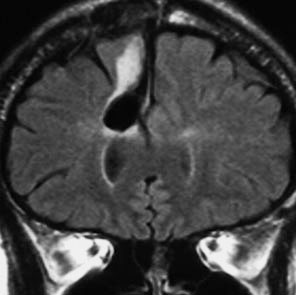

T2-FLAIR mismatch sign (T2とフレアの信号が違うこと)

protoplasmic astrocytomaに特徴的なMRI所見です。T2強調画像(左側)では白く(強い均一な高信号)見えます。でもフレア画像(右側)では白く縁取ったように見えます。びまん性星細胞腫の大きな特徴とされます。内部がとても柔らかいドロドロした腫瘍のこともあります。